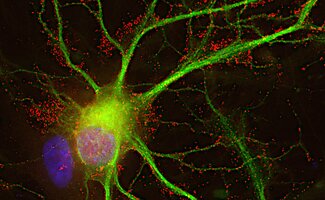

Cannabinoid receptors are transmembrane proteins that mediate the action of CBs.

Glutamate receptors are the most abundant type of excitatory neurotransmitter receptors in the mammalian CNS.

Receptor proteins include metabotropic, ionotropic and enzyme-linked hormone receptors.